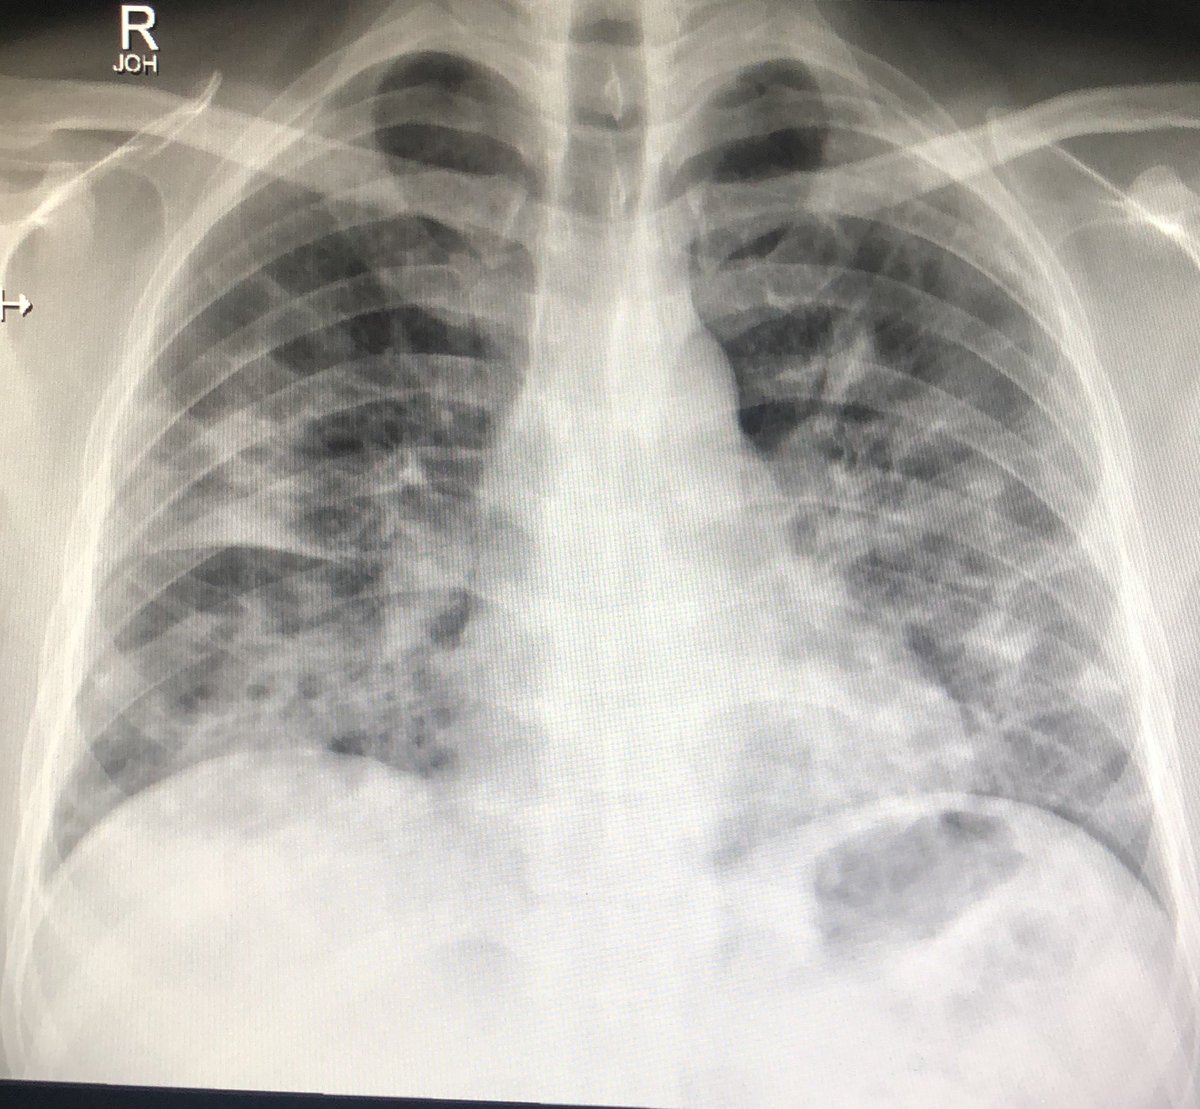

ثالثاً والأهم "أشعة الصدر" chest x-ray

لنحدد هل نزل الالتهاب على الصدر و ما هي حدته.

تنقسم الرئة لجزء أيمن يُقسم بدوره إلى فصين وأيسر يُقسم إلى ثلاثة فصوص ، كوفيد غالباً يبدأ التهابه من "الأطراف/الأضلاع" في الفصوص السفلية من الرئة وغالباً في الجهتين

هذه صور لأشعة صدر طبيعية ( سوداء والقلب في المنتصف ) وأشعة صدر غير طبيعية ، البياض الذي ترونه في الصور الأخرى هو الالتهاب ودرجاته تختلف بالطبع ، كم فص من الرئة أصيب ؟ وماهي الوظائف الحيوية للمريض وقتها و فحوصاته الأخرى